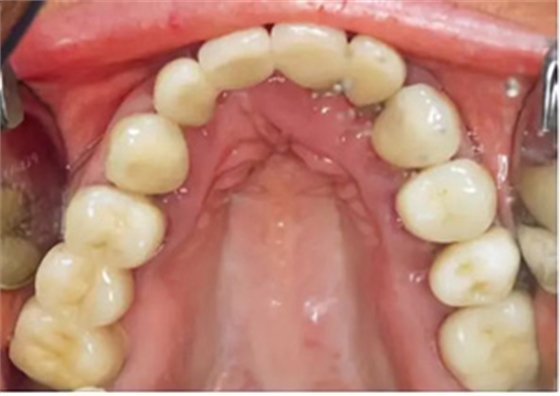

口外檢查未發(fā)現(xiàn)異常。牙齒和牙周狀態(tài)如圖1 和2-6所示??傮w來說,已有的修復(fù)體已不完善。第一次就診時(shí),檢查發(fā)現(xiàn)17、15、11、36、45 和46 號牙齒已缺失。16、14、12、27、37 和35 號牙齒已做過根管治療。所有剩余的牙齒牙髓活力測試均正常,叩診檢查未見異常。橋基牙37 已發(fā)生大面積的繼發(fā)齲,33 號牙齒齲壞和43 號牙齒繼發(fā)齲。16 和14 號牙齒根管充填不足且有根尖周炎。35 號牙齒的根管充填似乎是邊緣封閉、無氣泡,但也欠充。所有需要保留的牙齒的平均牙周附著喪失為5-6mm(最大9mm),探診深度(ST)為4-5mm(最大8mm)。27 號牙齒單獨(dú)的探診深度已達(dá)15mm。牙齦緣普遍松軟,下頜前牙舌側(cè)區(qū)域附著堅(jiān)硬的菌斑。整個(gè)邊緣牙齦發(fā)生炎癥性改變,特別是腭側(cè)區(qū)域。

圖2-圖6:2013 年10 月15 日口內(nèi)狀況。